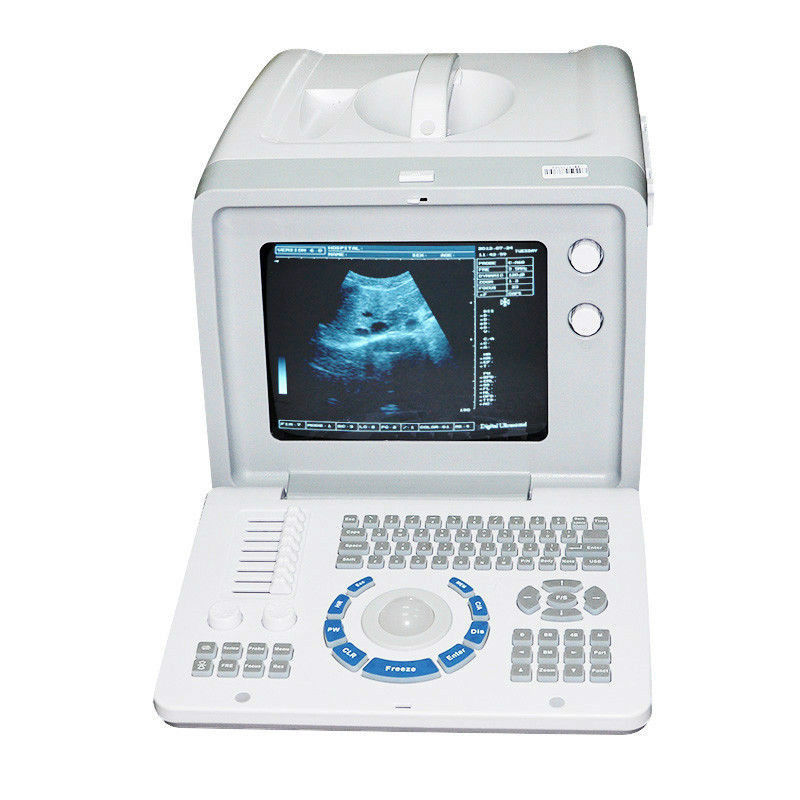

Innovative 3D Dynamic Imaging Capability

The new Ultrasound Scanner introduces groundbreaking 3D dynamic imaging technology, allowing for real-time visualization. This means that healthcare professionals can capture and analyze images as they happen, providing immediate information for diagnoses. Utilizing dual probes—convex and transvaginal—this device offers flexibility and precision, enhancing its usability in various medical settings. The advanced imaging helps doctors to examine structures and functions with clarity, making the diagnosis process more efficient.

User-Friendly Interface and Design

This ultrasound scanner is designed with ease of use in mind. The user-friendly interface simplifies navigation and operation, enabling healthcare providers to focus more on patient care rather than complex technology. Additionally, the ergonomic design ensures comfort during examinations, which is crucial when conducting transvaginal procedures. Because of these thoughtful features, medical staff can work quickly and effectively, minimizing patient discomfort.

Versatile Applications in Healthcare

The ultrasound scanner is suitable for a variety of applications, ranging from obstetrics to urology. This versatility is primarily because of the dual probe system, which allows for comprehensive examinations across different specialties. Healthcare providers can rely on this machine not just for routine check-ups but also for complex diagnostic tasks. Therefore, the scanner represents a significant advancement in medical imaging technology, ensuring better healthcare outcomes through precise and responsive imaging capabilities.